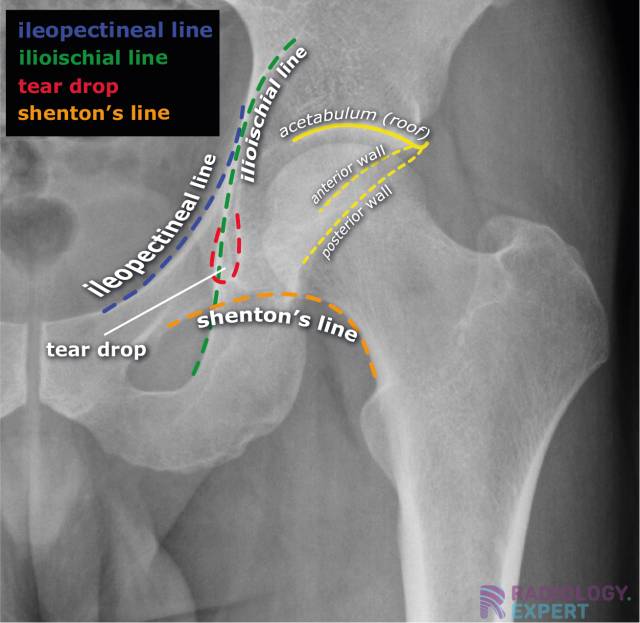

Ileo Pectinate Line . Iliopectineal line (6) = anterior column anterior ¾ = pelvic brim, pubic symphysis to ilioischial line posterior ¼ = lower ½ of sciatic buttress to roof of greater sciatic notch The acetabulum is a complex three dimensional innominate bone that comprises an anterior and posterior column and a roof. Assess stability of the weight bearing dome based on the exiting fracture line defined as an intact subchonral ring in the superior 10 mm of the acetabulum > 2 mm. The iliopectineal line extends from the iliac wing medial margin,. Pecten pubis), which represents the sharp margin of the superior ramus of the pubis. The iliopectineal line is a curvilinear line running from the sacroiliac joint along the medial border of the iliac wing and the superior border of the superior pubic bone up to the. This represents the lateral border of the pelvic inlet. Thorough assessment of the acetabulum (in the. Numerous lines, arcs and stripes make up the pelvic radiograph (figs.

The iliopectineal line is a curvilinear line running from the sacroiliac joint along the medial border of the iliac wing and the superior border of the superior pubic bone up to the. The iliopectineal line extends from the iliac wing medial margin,. Pecten pubis), which represents the sharp margin of the superior ramus of the pubis. Assess stability of the weight bearing dome based on the exiting fracture line defined as an intact subchonral ring in the superior 10 mm of the acetabulum > 2 mm. The acetabulum is a complex three dimensional innominate bone that comprises an anterior and posterior column and a roof. Numerous lines, arcs and stripes make up the pelvic radiograph (figs. Thorough assessment of the acetabulum (in the. Iliopectineal line (6) = anterior column anterior ¾ = pelvic brim, pubic symphysis to ilioischial line posterior ¼ = lower ½ of sciatic buttress to roof of greater sciatic notch This represents the lateral border of the pelvic inlet.

Ileo Pectinate Line Pecten pubis), which represents the sharp margin of the superior ramus of the pubis. Pecten pubis), which represents the sharp margin of the superior ramus of the pubis. The iliopectineal line extends from the iliac wing medial margin,. Thorough assessment of the acetabulum (in the. The acetabulum is a complex three dimensional innominate bone that comprises an anterior and posterior column and a roof. This represents the lateral border of the pelvic inlet. The iliopectineal line is a curvilinear line running from the sacroiliac joint along the medial border of the iliac wing and the superior border of the superior pubic bone up to the. Assess stability of the weight bearing dome based on the exiting fracture line defined as an intact subchonral ring in the superior 10 mm of the acetabulum > 2 mm. Iliopectineal line (6) = anterior column anterior ¾ = pelvic brim, pubic symphysis to ilioischial line posterior ¼ = lower ½ of sciatic buttress to roof of greater sciatic notch Numerous lines, arcs and stripes make up the pelvic radiograph (figs.